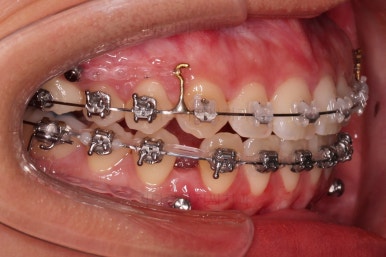

우선 가지런하게 하는 작업을 했고요.

교합을 맞춰야 하기 때문에 윗니는 통째로 약간 뒤로 밀어줍니다.

아랫니는 앞니가 더이상 뒤로 들어가지 않도록 어금니를 앞으로 당기는 셋팅을 해줍니다.

그래서 위아래 좌우 모두 다른 용도로 미니스크류가 식립되었고요.

각각의 방향으로 계속 당겨줍니다.

윗니의 배열과 위치는 거의 완성이 되었고요.

아래는 아직 틈이 많이 보이죠.

어금니를 부산치아교정 통해 계속 앞으로 당겨줍니다.